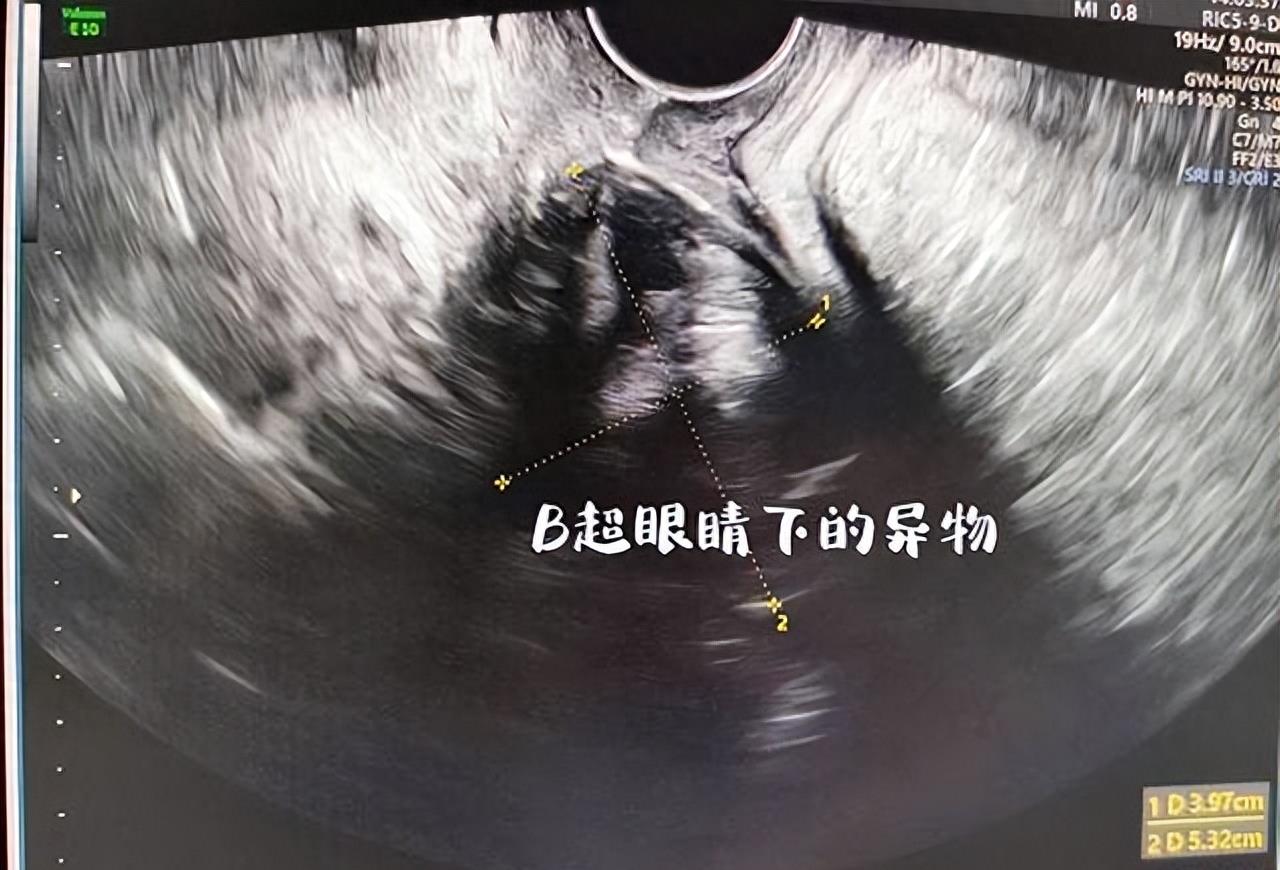

在医院,经过检查,医生确定小杨体内存在异物,并且炎症反应已经显著。医生提醒小杨,将异物长时间放置在体内不仅可能引发感染,还可能对生育功能产生不良影响。医生的话语充满了教育意味,同时也显露出对年轻人冲动行为的无奈。

为了将异物取出,医生经过一系列的检查,最终决定进行手术取出。在手术中,医生用了不少功夫,才将这个化妆品盖子取了出来。整个过程不仅是对小杨身体的一种伤害,更是对她心理的一次教育。